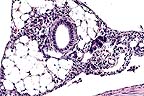

Perivascular cuffing of a cerebellar blood vessel with moderate nubmers of lymphocytes and lesser numbers of macrophages and plasma cells in a horse infected with equine lentivirus. (HE, 400X, 45K)

Contributor's Diagnosis and Comments: Severe nonsuppurative meningoencephalitis and choroid-plexitis with microgliosis. Lentivirus of equine infections anemia (EIA).

The CNS lesion typically has an "inside out" pattern, whereby the inflammation is severe around the ventricular system. In this horse, that was best seen in the spinal cord. This horse tested negative for sarcocystosis, neosporsosis, VEE and EEE.

AFIP Diagnosis: Cerebellum, brain stem, midbrain, and choroid plexus: Choriomeningoencephalitis, nonsuppurative, multifocal, moderate, Appaloosa, equine.